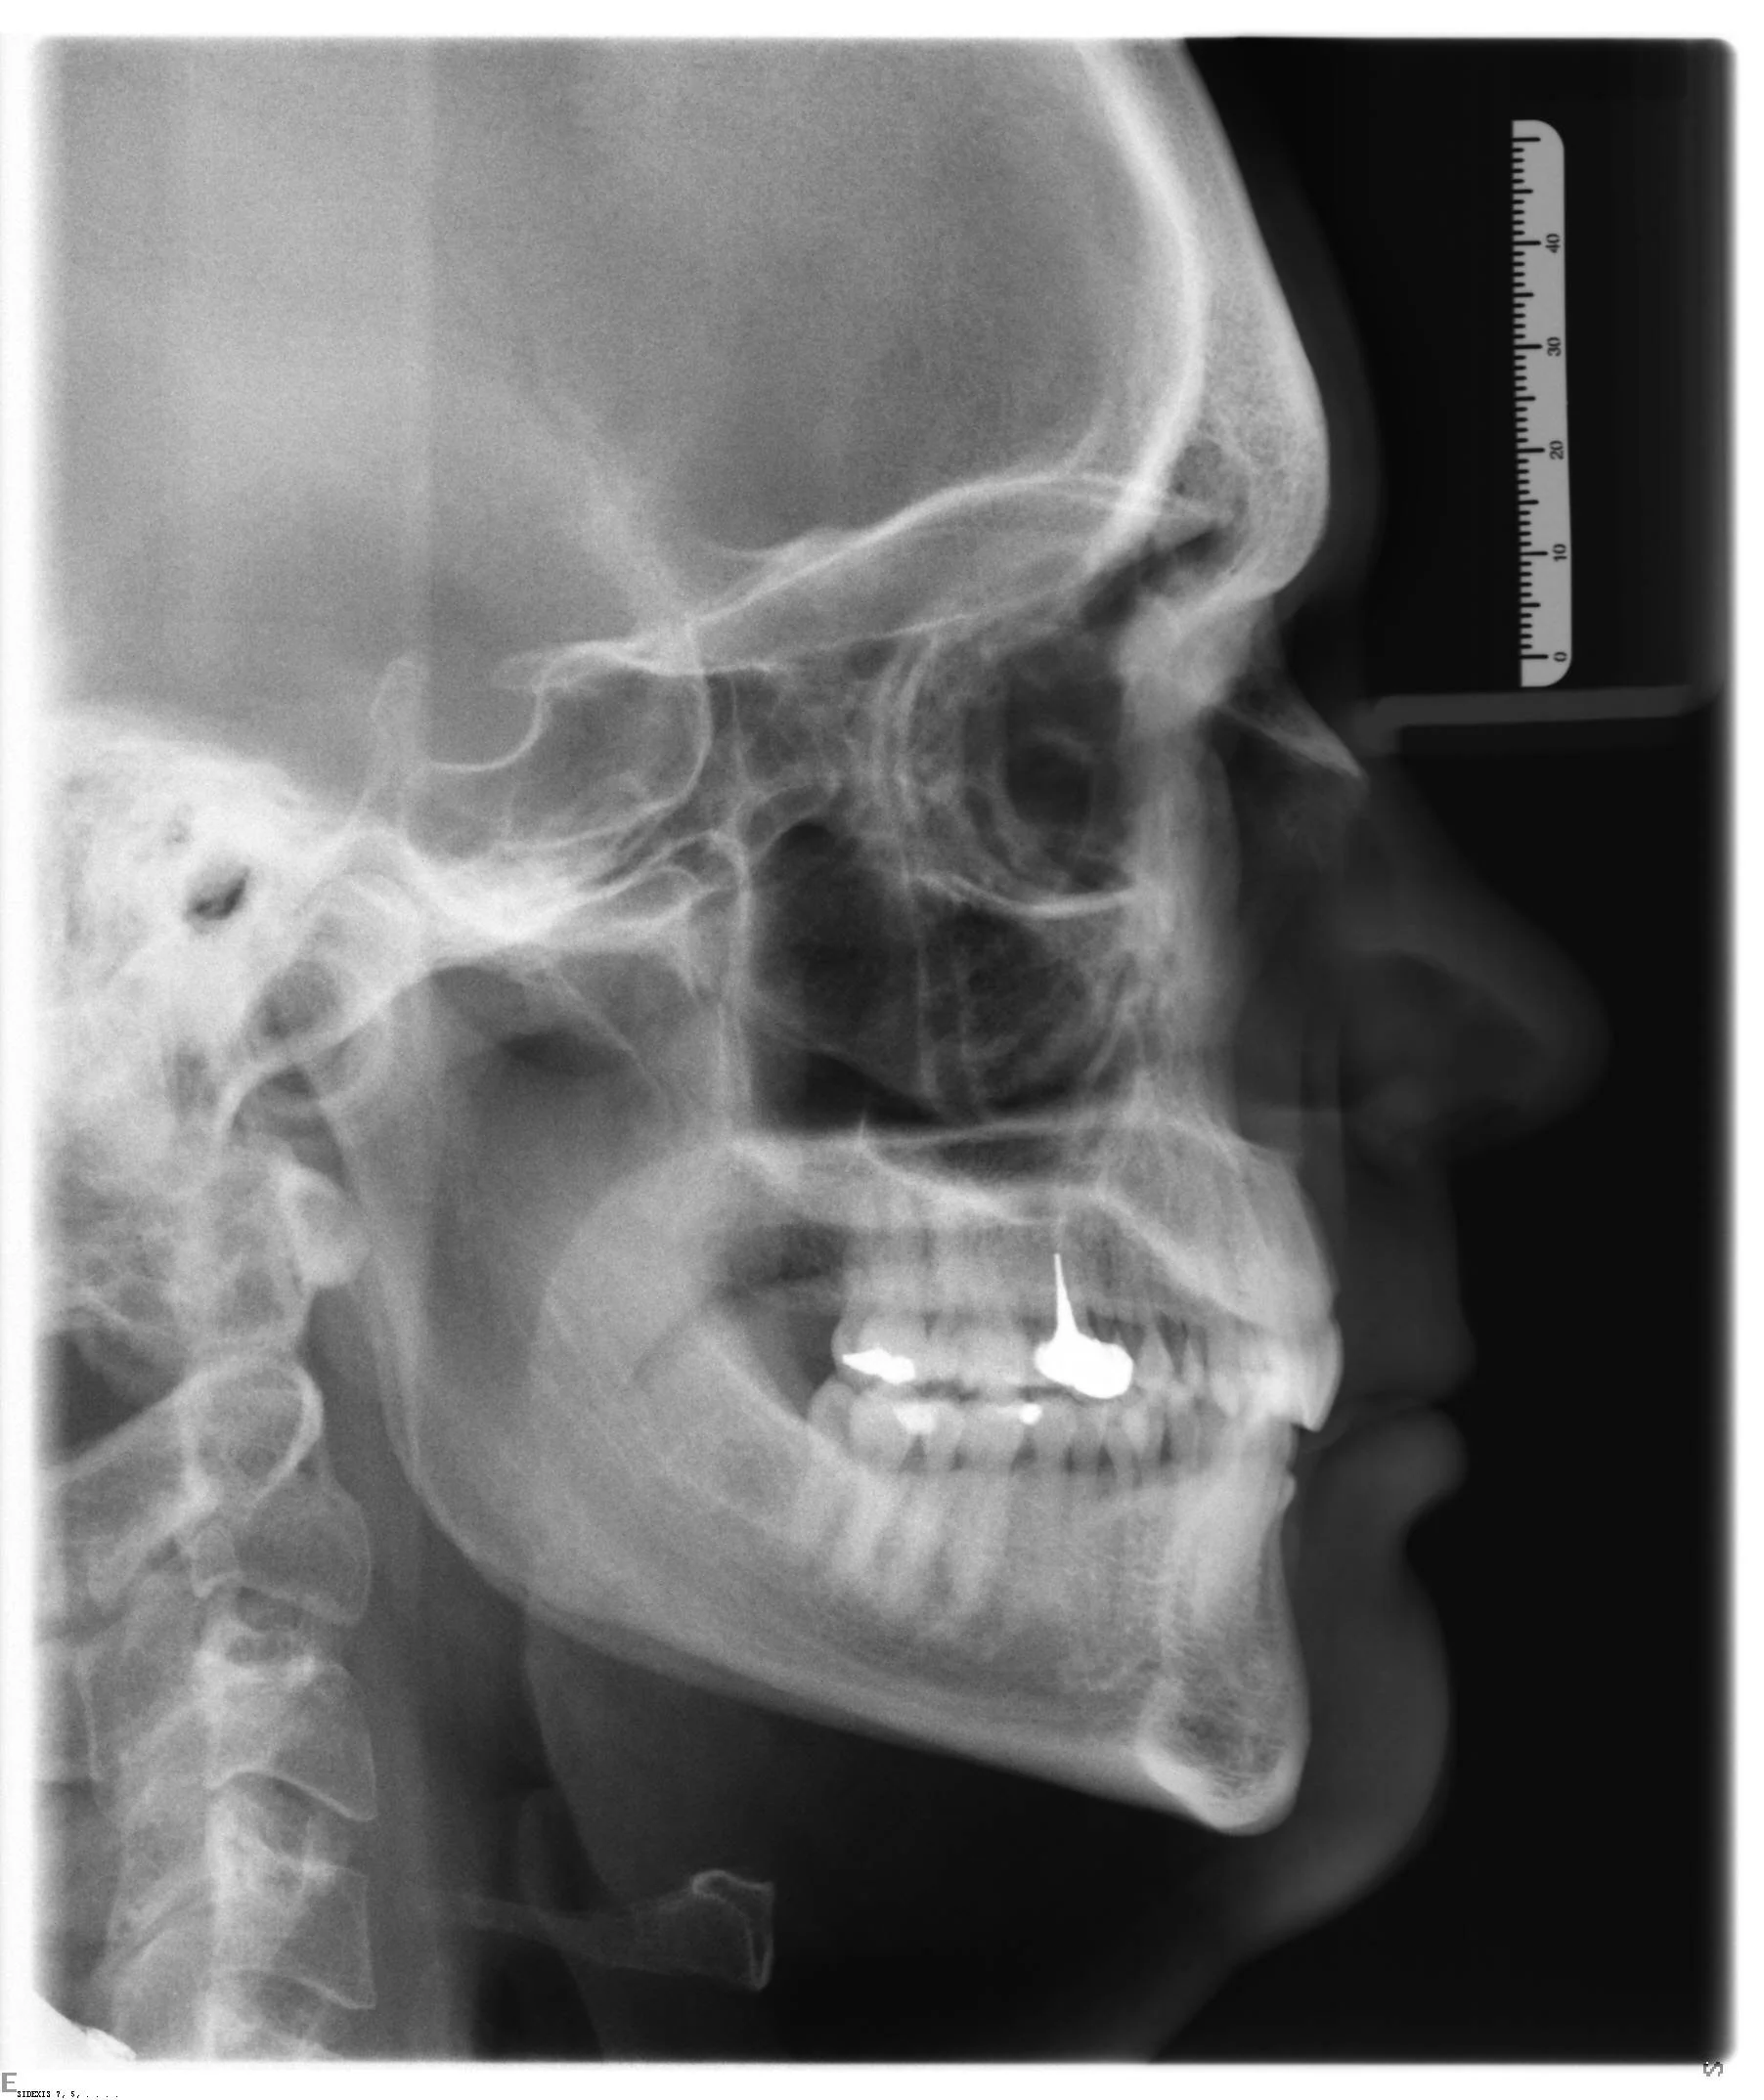

ceph class II.JPG